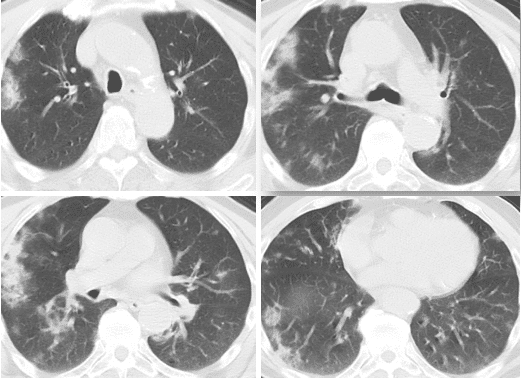

二、影像检查

初次胸部CT提示双侧肺野可见多发团、片状高密度影,结合COVID-19检测情况,支持新型冠状病毒性肺炎诊断。